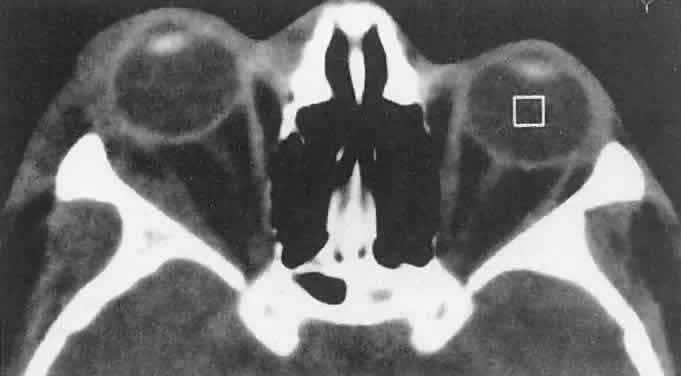

CT discloses a single or multilobulated mass, which represents only the blood cyst portion of the tumor (Fig. 14). Individual lobules may have different radiodensities depending on the presence of clots or liquefied blood within each cyst (Fig. 15). A generalized increase in orbital dimensions suggests a long-standing, probably congenital process. Echography may help differentiate the cystic components of lymphangioma from cellular rhabdomyosarcoma. Echography shows the blood cysts to be acoustically inactive spaces, with extremely low internal reflectivity (Fig. 16). Clots within the cysts can increase internal heterogeneity, however. MRI has virtually eliminated the need for diagnostic biopsy in this condition, because of its ability to show differing magnetic properties of suspended, degrading blood products (Fig. 17).

Fig. 16. Standardized A-scan echography shows low internal reflectivity and no decrement in sound energy transmission, which is consistent with a fluidlike cystic structure.

Fig. 17. MRI scan of a 17-year-old girl with abrupt-onset proptosis. Multilobulated cystic spaces with fluid-fluid levels suggest recent hemorrhage within a previously unrecognized lymphangi-oma.